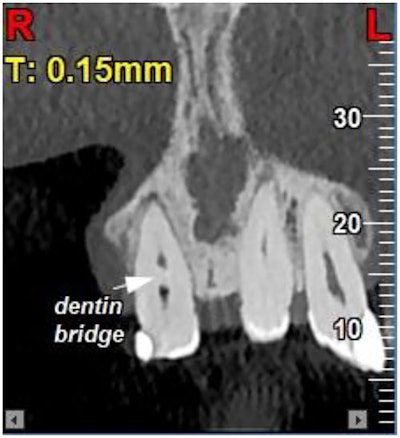

Cone-beam computed tomography (CBCT) revealed that the dentin bridge preserved the vitality of the tooth’s apical pulp. The man underwent a root canal limited to the necrotic coronal pulp up to the dentin bridge and restoration with a composite. A follow-up x-ray at three months showed treatment stability, the authors wrote.

The man had tooth discoloration after dental trauma. An exam revealed coronal pulp necrosis, and periapical radiography and CBCT confirmed internal resorption in the coronal pulp chamber with a spontaneously formed dentin bridge, the authors wrote.

The dentin bridge appeared to separate the necrotic coronal pulp from vital tissue. This thick barrier likely added to the preservation of apical pulp vitality, which was proven by the lack of apical pathosis and a normal apical canal configuration as shown on the CBCT, they wrote.

Figure 3: Coronal view of a CBCT image shows the dentin bridge separating the necrotic coronal pulp from the vital apical pulp.